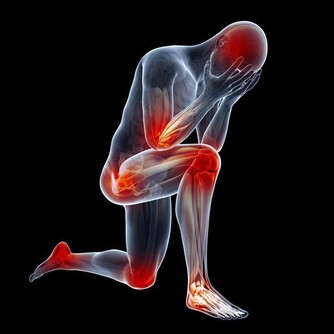

關節病是可以困擾老中青三代的常見的骨科疾病,其中,膝關節作為身體重要的支撐及活動結構,

因運動不當或隨著年紀變大,膝關節出現損傷的機率往往較其他關節更大。

1、膝關節,是由很多小夥伴共同組成的。

組成膝關節的小夥伴有骨頭、軟骨、肌肉、韌帶和肌腱,構成膝關節的任何一個成分出了問題,都壞導致膝關節疼痛或不能行動。